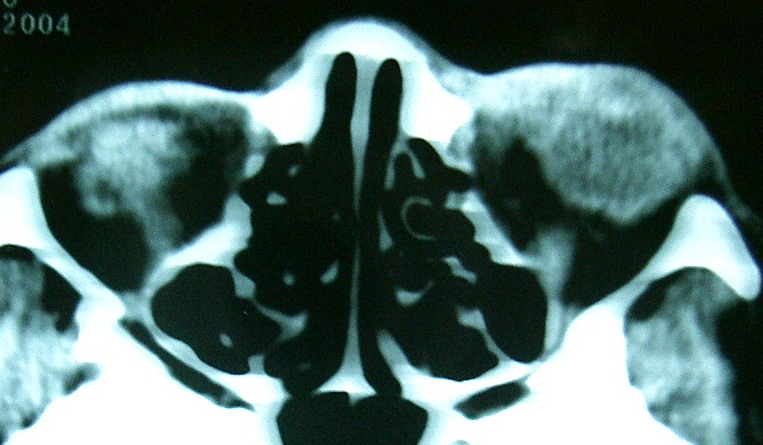

此主题相关图片如下:

按此在新窗口浏览图片

眼眶冠扫,平扫CT:

左眼球内上方可见不规则软组织块影,大小约2.5*1.0CM,与邻近组织分界不清,相邻之内直肌、上直肌增粗,眼环正常,眶壁骨质无破坏,左上颌窦底部可见粘膜增厚,其余副鼻窦未见异常。

IMP:1,左眼眶肿物;2,左上颌窦炎